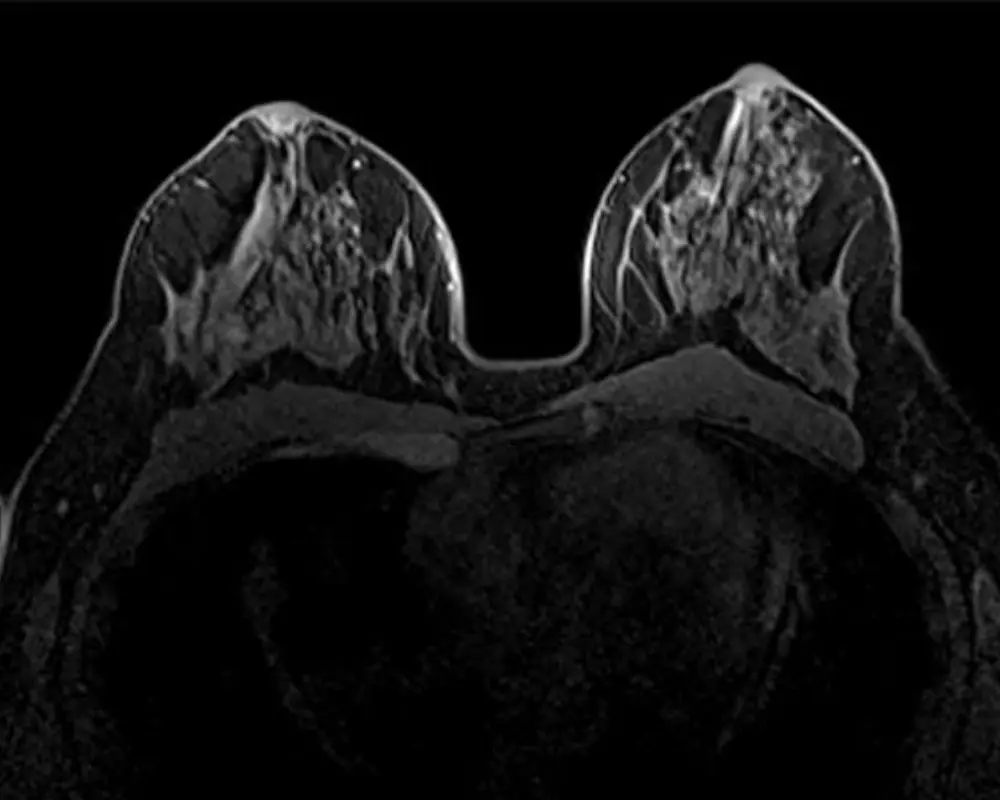

Breast MRI is a highly detailed imaging method used to examine breast tissue more closely than standard imaging. It is often recommended when additional clarity is needed, especially in cases involving dense breast tissue or areas that require further evaluation.

Breast MRI is often recommended when a more detailed view of breast tissue is needed beyond standard imaging. It provides deeper insight into areas that may not be clearly visible on a mammogram or ultrasound, especially when further evaluation is required.

At Maximum Resolution Imaging Center, our breast MRI in Houston TX and Richmond TX helps detect conditions such as breast lesions, abnormal tissue changes, implants evaluation concerns, and areas that may require closer examination. This advanced imaging supports early detection and helps guide the next steps in care with greater clarity and confidence.

Detailed Breast Imaging

Breast MRI provides highly detailed images of breast tissue, helping identify abnormalities that may not be visible through other imaging methods. It supports accurate diagnosis and better evaluation.

Accurate Breast MRI Imaging

During your breast MRI scan, high-resolution images are captured to evaluate breast tissue and detect abnormalities. This supports accurate diagnosis and helps guide better treatment and care decisions.